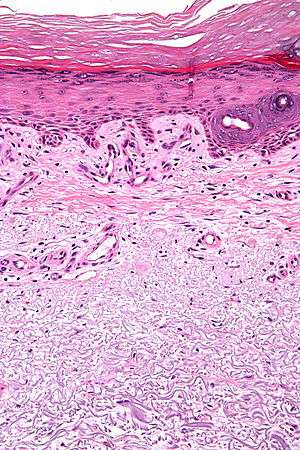

Micrograph showing solar elastosis - grey, jumbled spaghetti-like material on bottom of image. H&E stain. | |

In the earlier stages of actinic elastosis, elastic fiber proliferation can be seen in the dermis. As the condition becomes more established, the collagen fibers of the papillary dermis and reticular dermis become increasingly replaced by thickened and curled fibers that form tangled masses and appear basophilic under routine haematoxylin and eosin staining. These fibers stain black with the Verhoeff stain.[1]